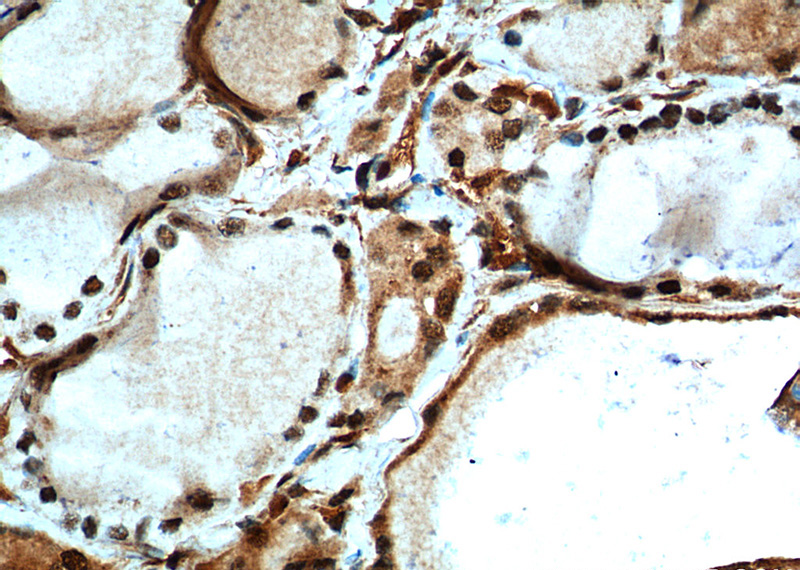

Immunohistochemistry of paraffin-embedded human thyroid cancer tissue slide using Catalog No:112918(MYCN Antibody) at dilution of 1:200 (under 40x lens). heat mediated antigen retrieved with Tris-EDTA buffer(pH9).